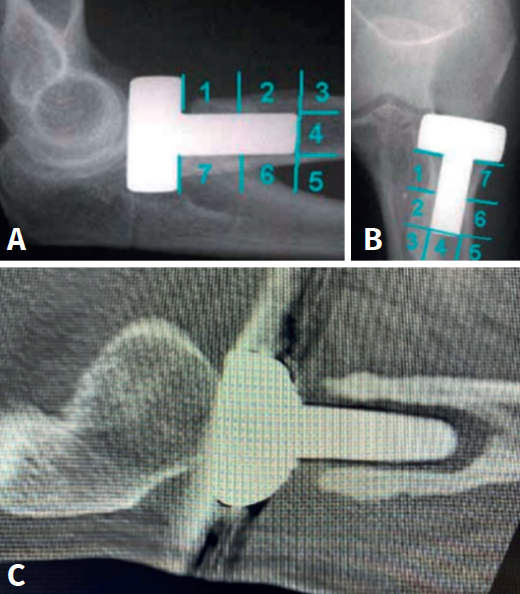

Clínicamente, puede manifestarse por dolor lateral, chasquidos y déficit del balance articular. Mediante radiografías anteroposterior y anterior podemos determinar la existencia de áreas radiolúcidas alrededor del vástago, atendiendo a la clasificación de Gruen modificada(16): aflojamiento leve cuando 1 o 2 zonas están afectadas, aflojamiento moderado cuando afecta de 3 a 6 zonas y aflojamiento grave cuando las 7 zonas están afectadas (Figuras 3 A y B). En la tomografía axial computarizada (TAC) será posible apreciar reabsorción del cuello, áreas de osteólisis y movilización del implante (Figura 3C). La reabsorción del cuello como consecuencia de la transmisión de las cargas a la diáfisis a través de la prótesis es un fenómeno frecuente a partir del séptimo mes, que habitualmente se estabiliza a los 15 meses y, si está limitada al cuello, no compromete la estabilidad del implante(17).